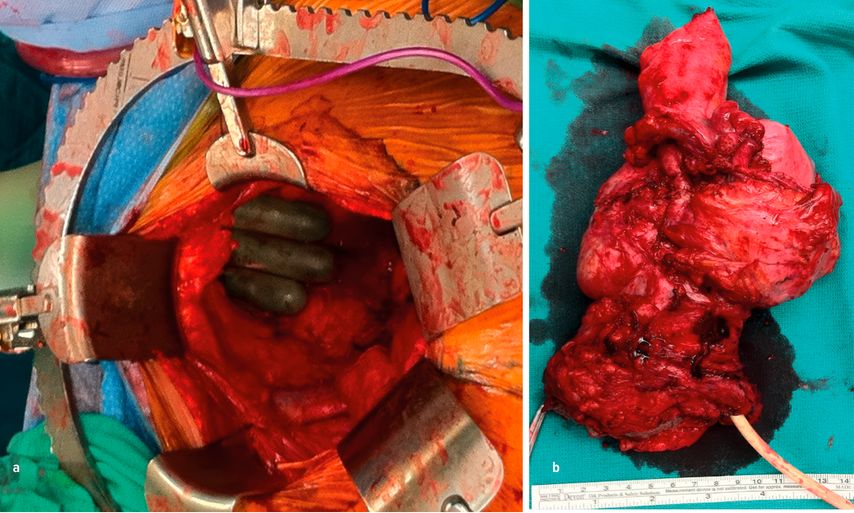

Auch bei lokalen Rezidiven sowie bei Patientinnen, die bereits eine pelvine Bestrahlung erhalten haben, spielt die Chirurgie eine wichtige Rolle. In ausgewählten Fällen, in denen die Erkrankung vollständig und radikal entfernt werden kann, kann eine Exenteration zu einer kurativen Behandlung führen. Die Exenteration ist ein sehr radikaler Eingriff, bei dem die pelvinen Organe entfernt werden. Es kann sich dabei um eine vordere (Blase und Gebärmutter), hintere (Gebärmutter und Rektum) bzw. totale (Blase, Gebärmutter und Rektum) Exenteration sowie eine supra- bzw. infralevatorische (Levator ani) handeln (Abb. 3a und b).

Abb. 3a und b:a: Totale infralevatorische Exenteration, b: Präparat einer totalen infralevatorischen Exenteration (Blase, Uterus, Vagina und Rektum)

Nach der destruktiven Phase folgt eine rekonstruktive Phase mit Anlage eines Ileum- bzw. ileokolischen Conduits, einer Kolostomie sowie gegebenenfalls einer Neovagina.